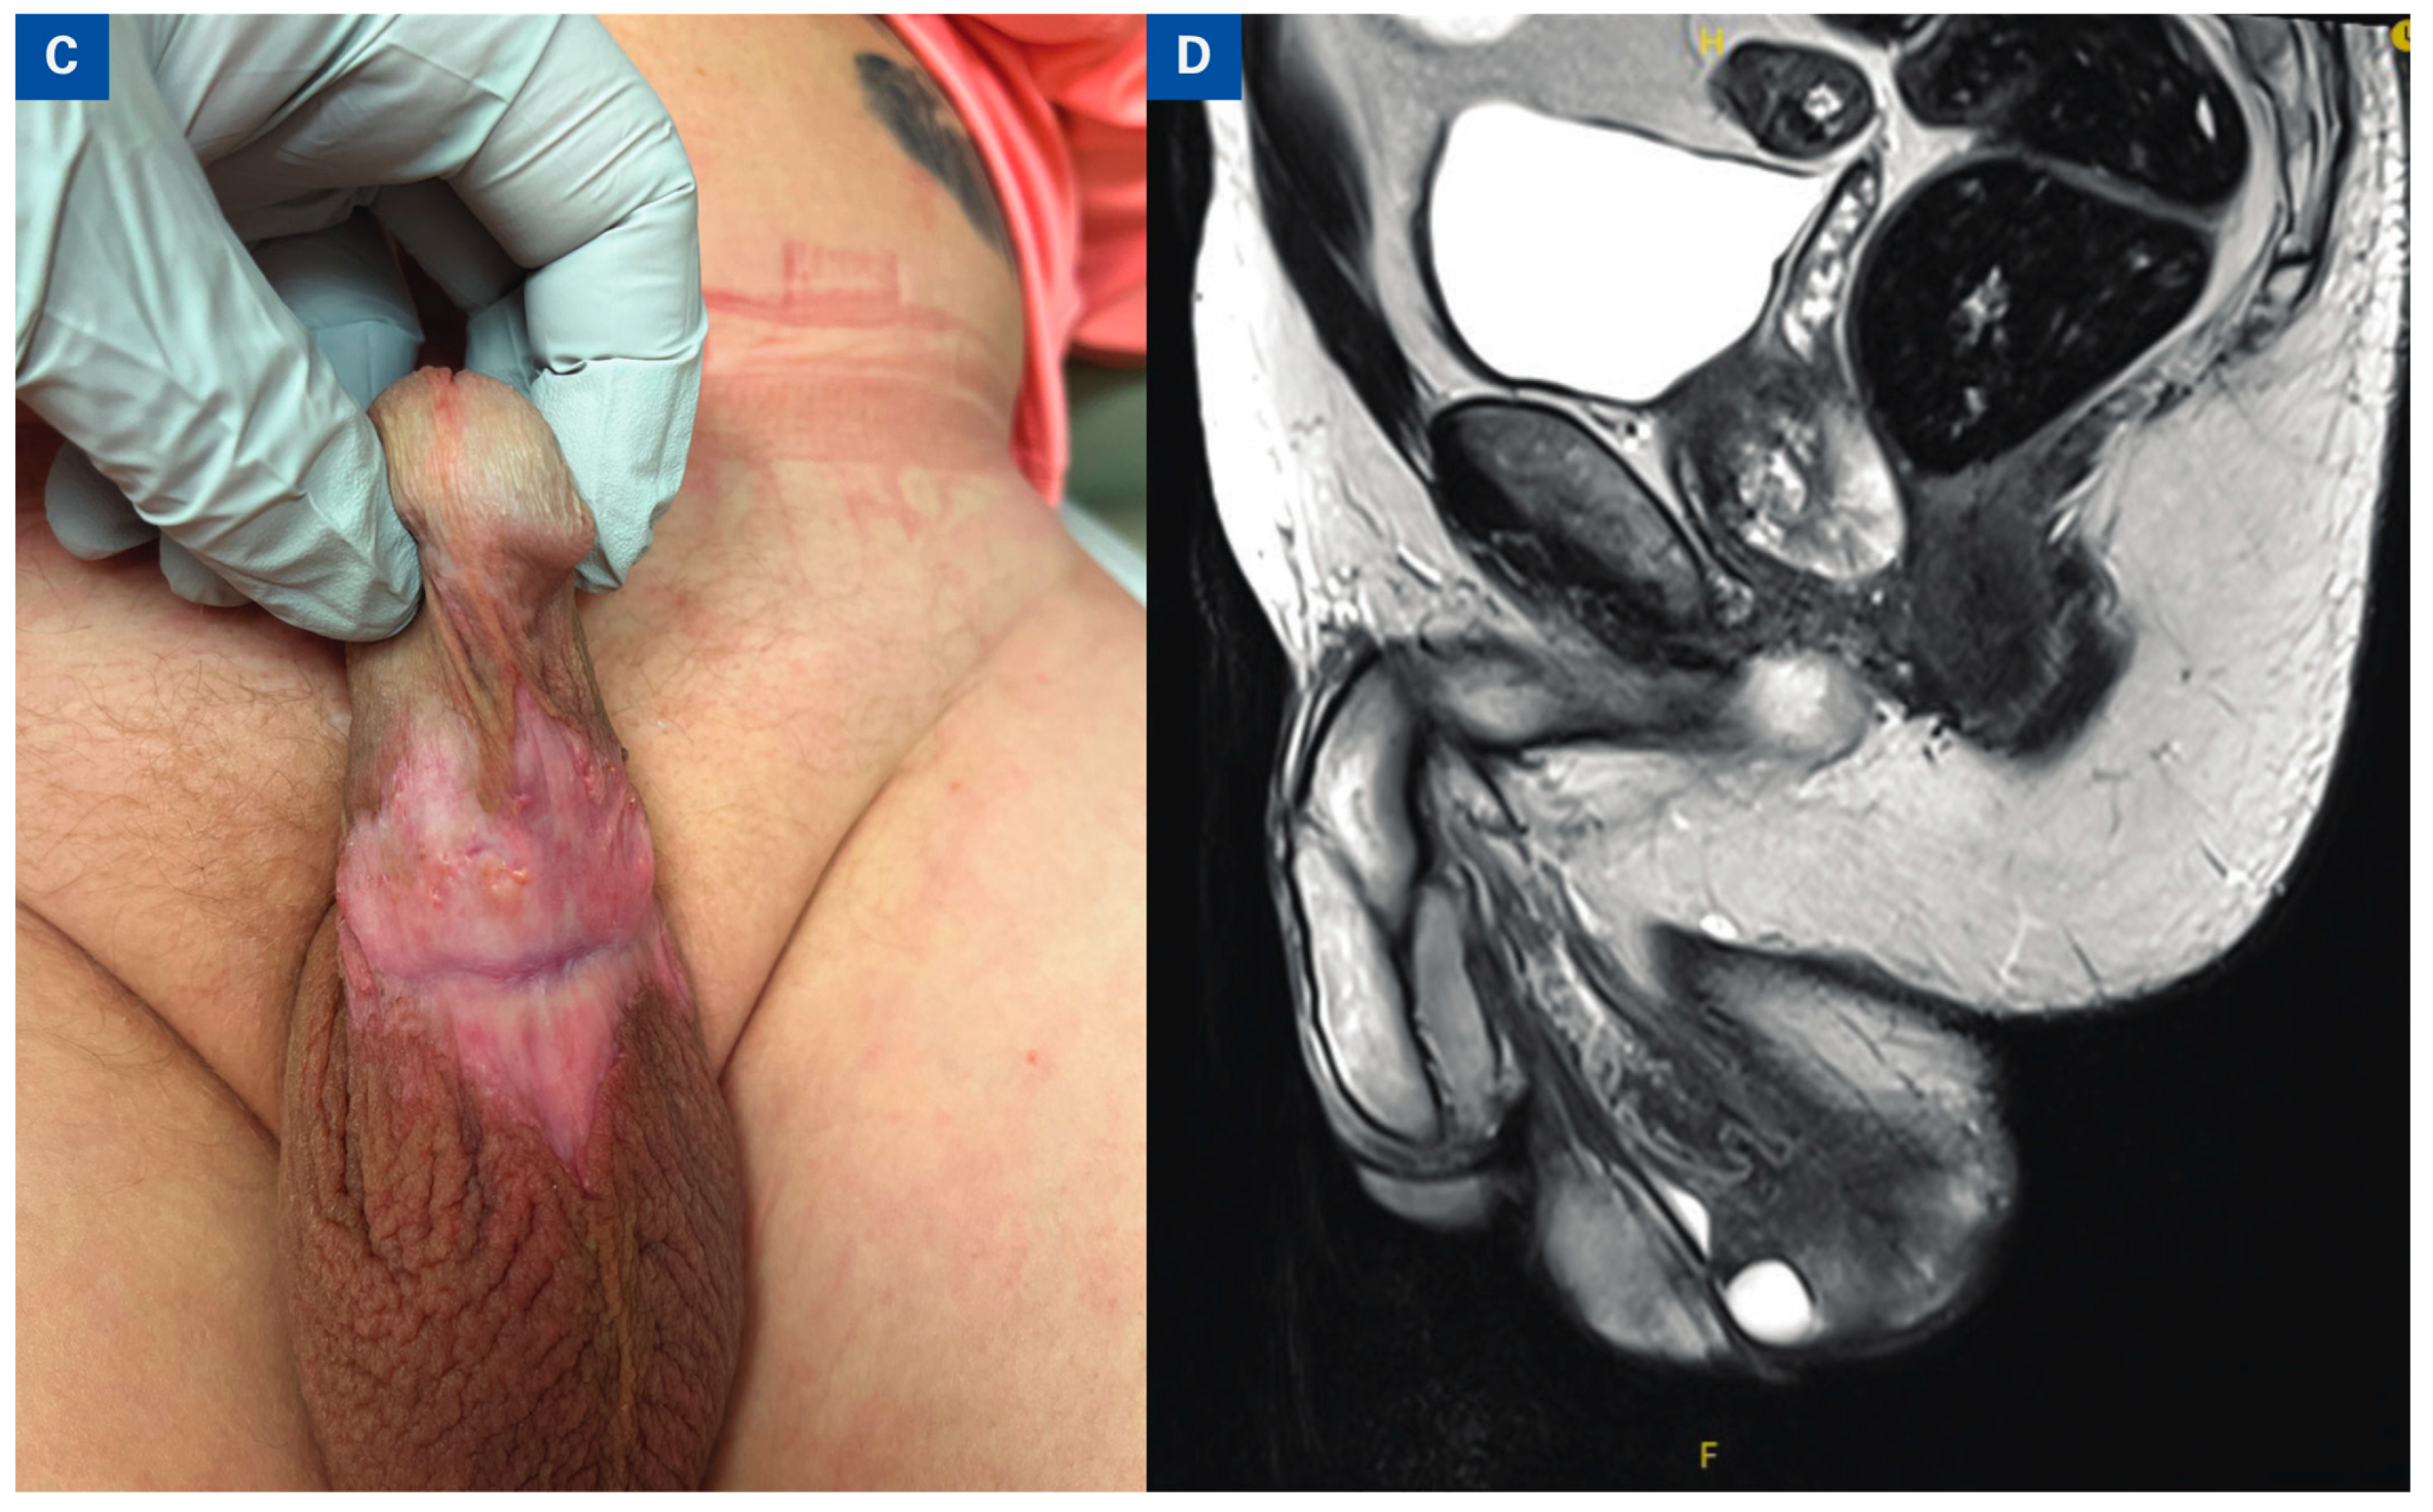

Complete Response of Primary Penile Tumor With Induction Paclitaxel, Ifosfamide, and Cisplatin (TIP) Chemotherapy